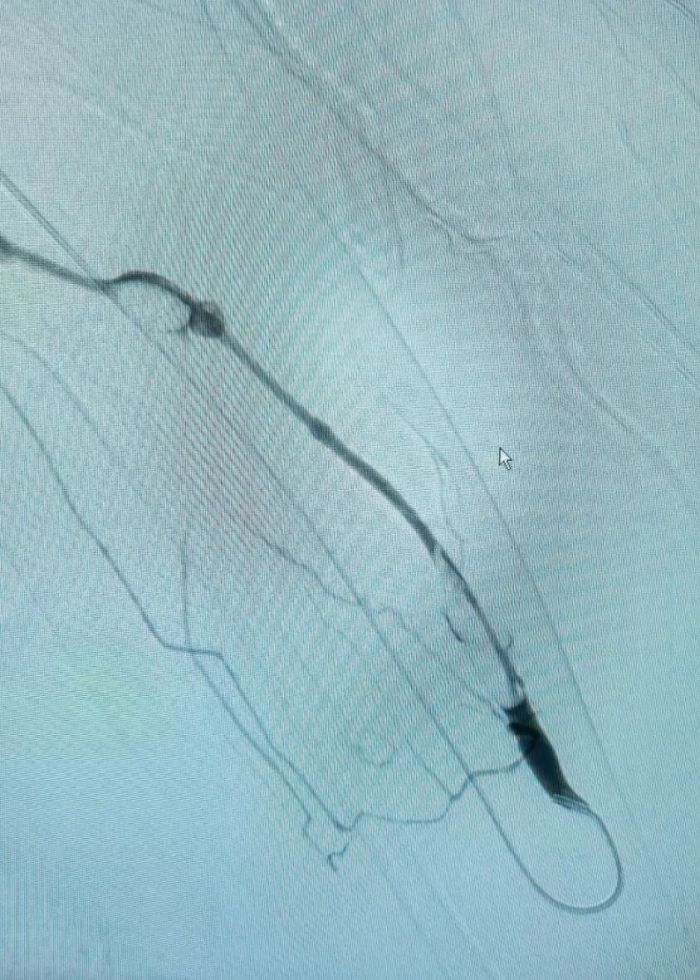

术后.jpg

术后影像

另一名患者则接受了介入下动静脉内瘘开通术,术后自体动静脉内瘘震颤恢复,血管通路功能得到有效重建,目前正接受规范溶栓治疗。目前,两名患者术后恢复情况良好,治疗效果得到了患者及家属的高度认可。